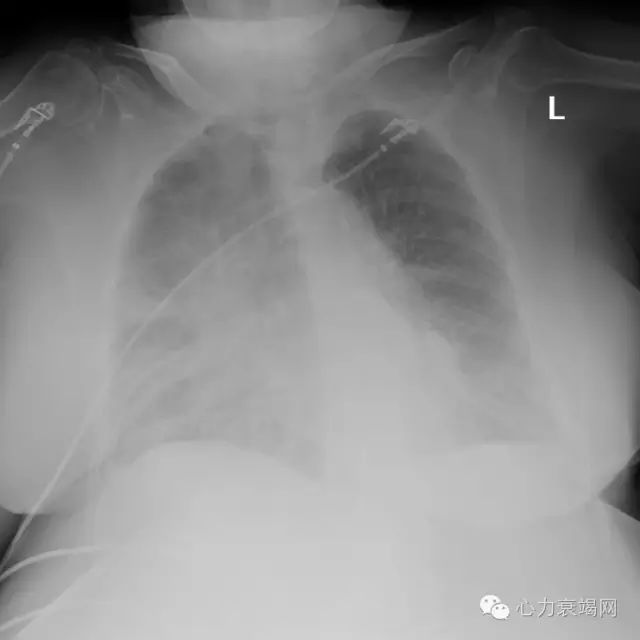

◆李XX,女性,88岁

◆主因发作性胸闷胸痛5天入院。

◆2016年4月26日无明显诱因出现胸闷胸痛,持续约1小时候自行缓解,但此后逐渐出现不能平卧,感气短,外院检查提示心肌酶升高,心电图提示II、III、aVF导联Q波形成。

◆入院查体:血压132/87mmHg,心率81次/分 ,型肥胖,坐位,颈静脉未见明显怒张,双肺呼吸音粗,双肺底可闻及湿罗音,肝脏未触及,腰骶部及双下肢无水肿。

◆诊断“急性下壁心肌梗死,Killips III级,高血压3级”

胸片(2016-5-1)

超声心动图

◆左心室舒张末内径45mm

◆左室射血分数41%

◆左房前后径41mm

◆下腔静脉24(14-21mm)

◆左房扩大,余房室腔大小形态正常,静息状态下可见下壁室壁变薄,运动减弱,左室整体功能减低。

◆印象:节段性室壁运动障碍(下壁),左室整体功能减低,二尖瓣中度反流